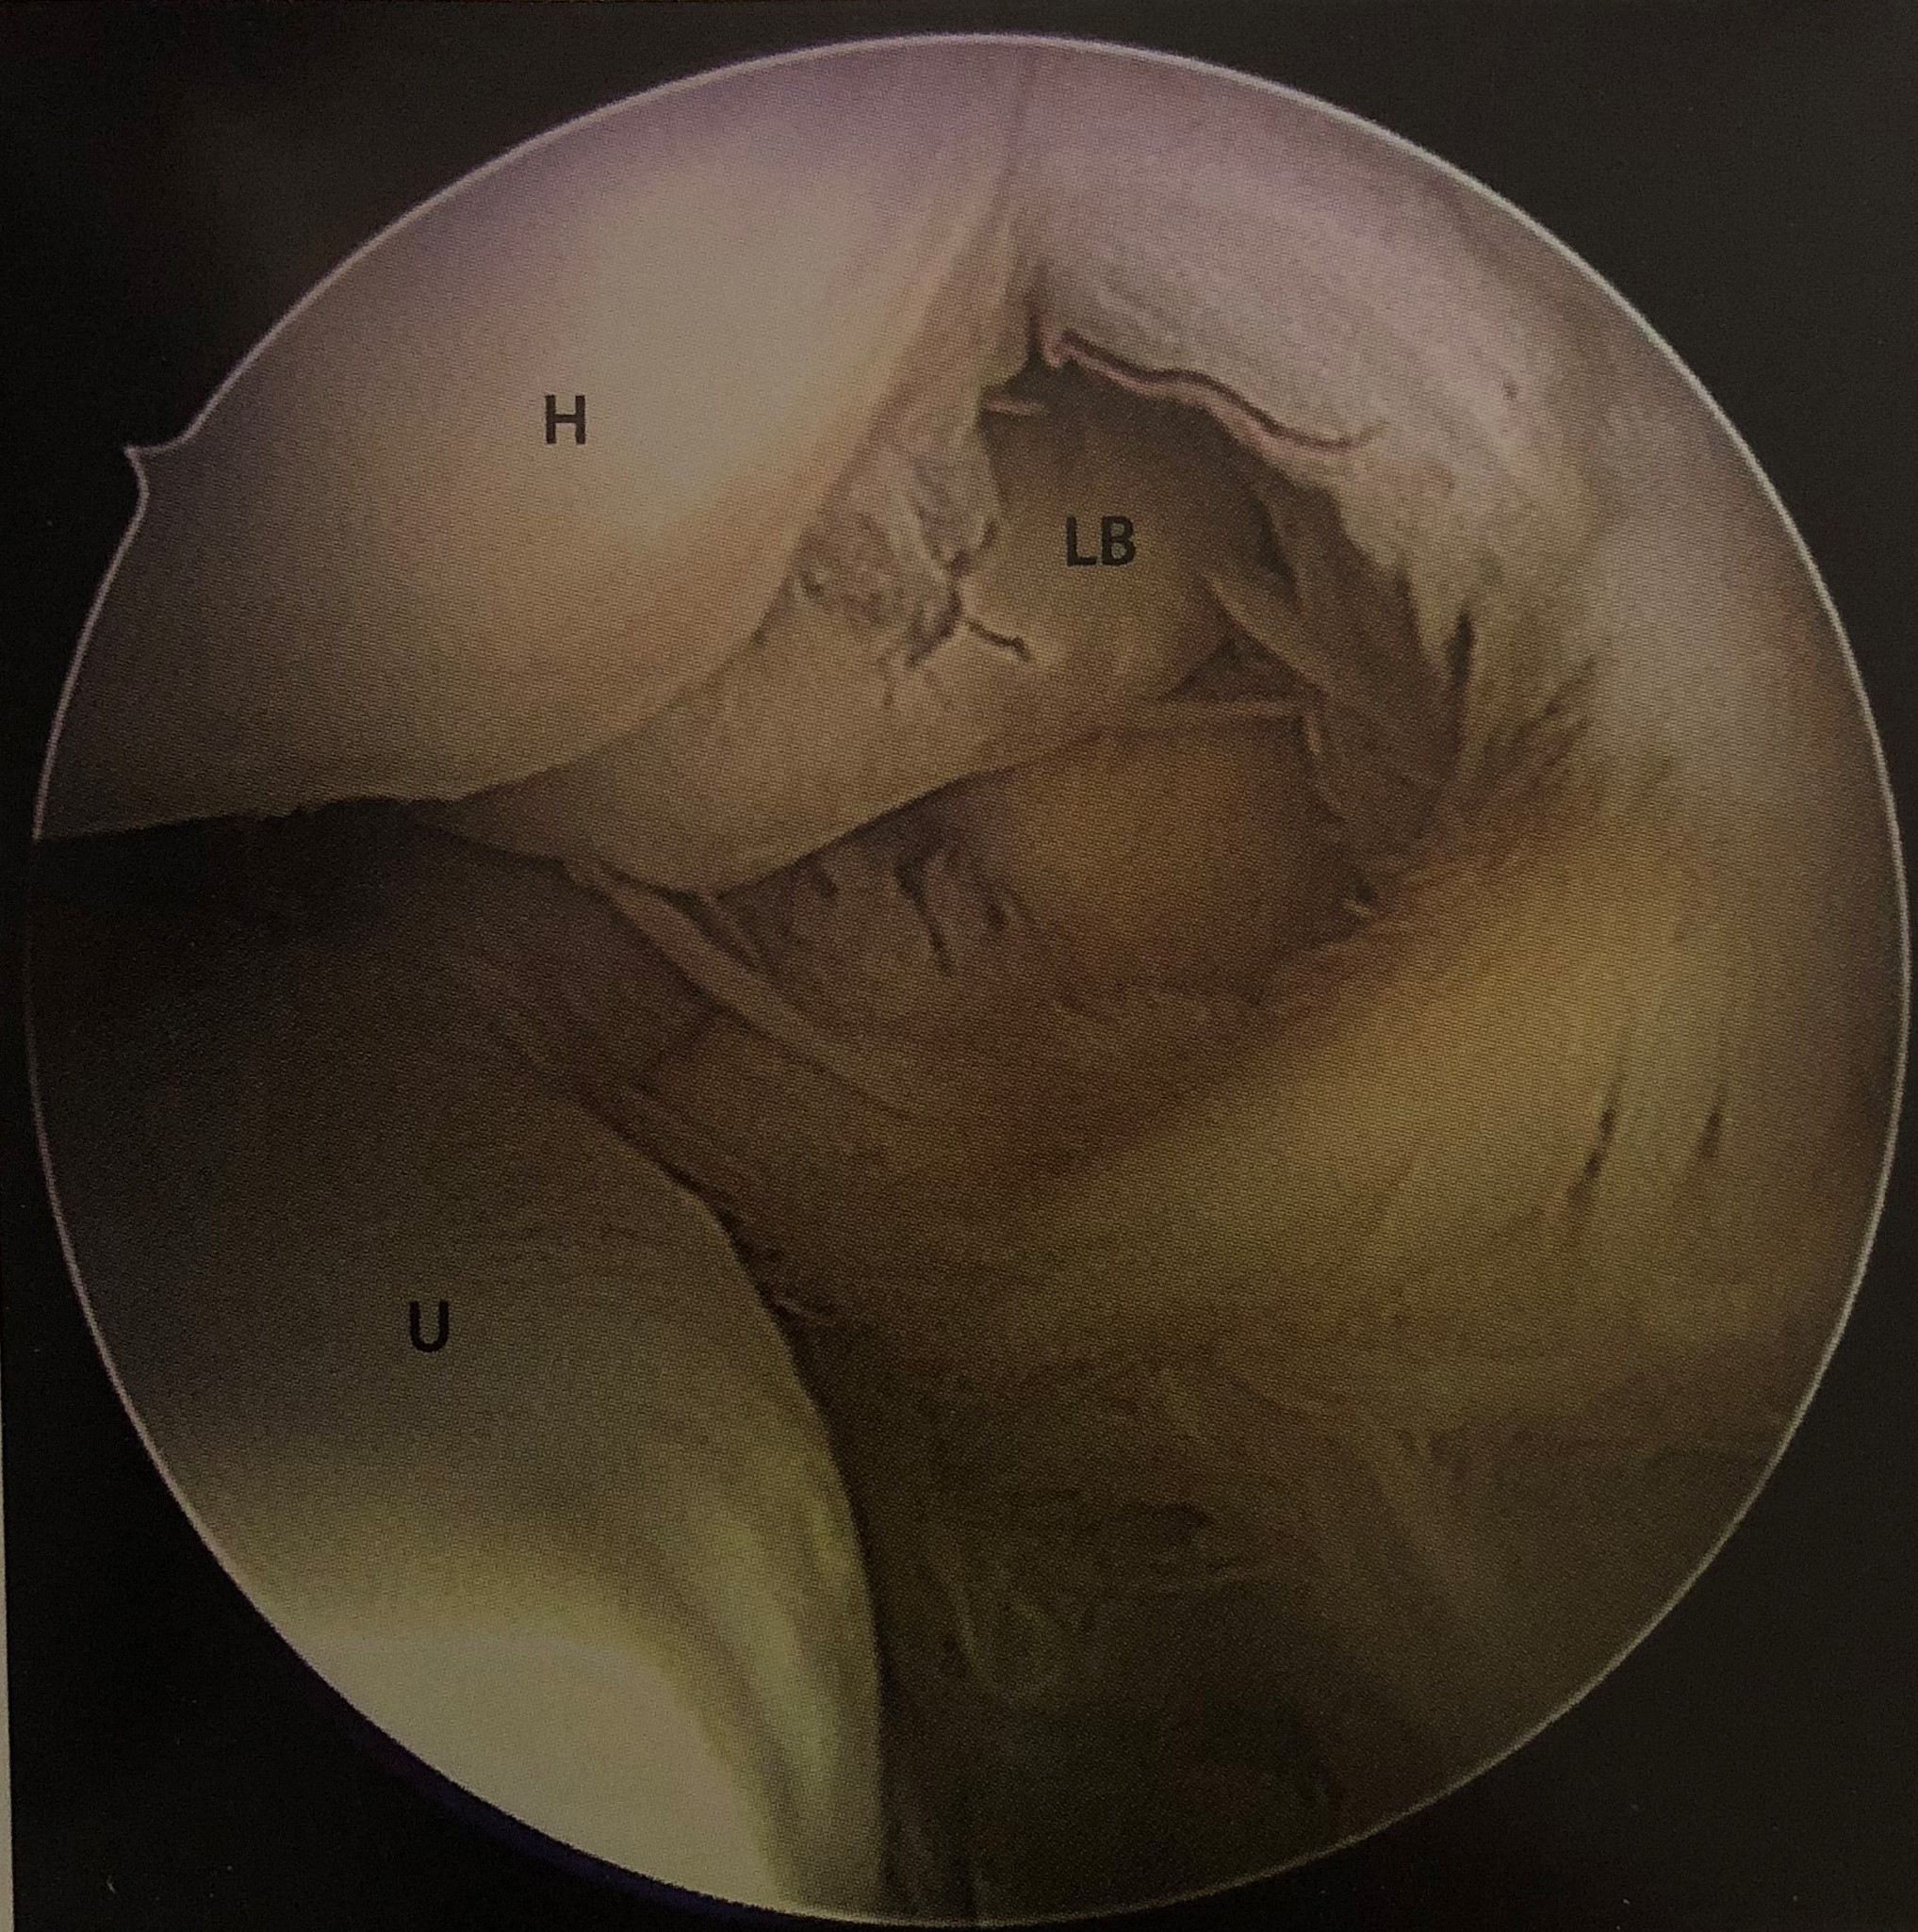

Upload Date: January 23, 2019 Full Size Image Dimensions: 2035 × 2050 Image Parent Post: ΑΡΘΡΟΣΚΟΠΗΣΗ ΑΓΚΩΝΑ

Β.Διαχωριστική οστεοχονδρίτιδα